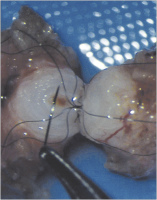

Refertilisierung und ICSI bei obstruktiver Azoospermie

Journal für Reproduktionsmedizin und Endokrinologie - Journal of Reproductive Medicine and Endocrinology 2010; 7 (5): 408-412 Volltext (PDF) Summary Praxisrelevanz Abbildungen